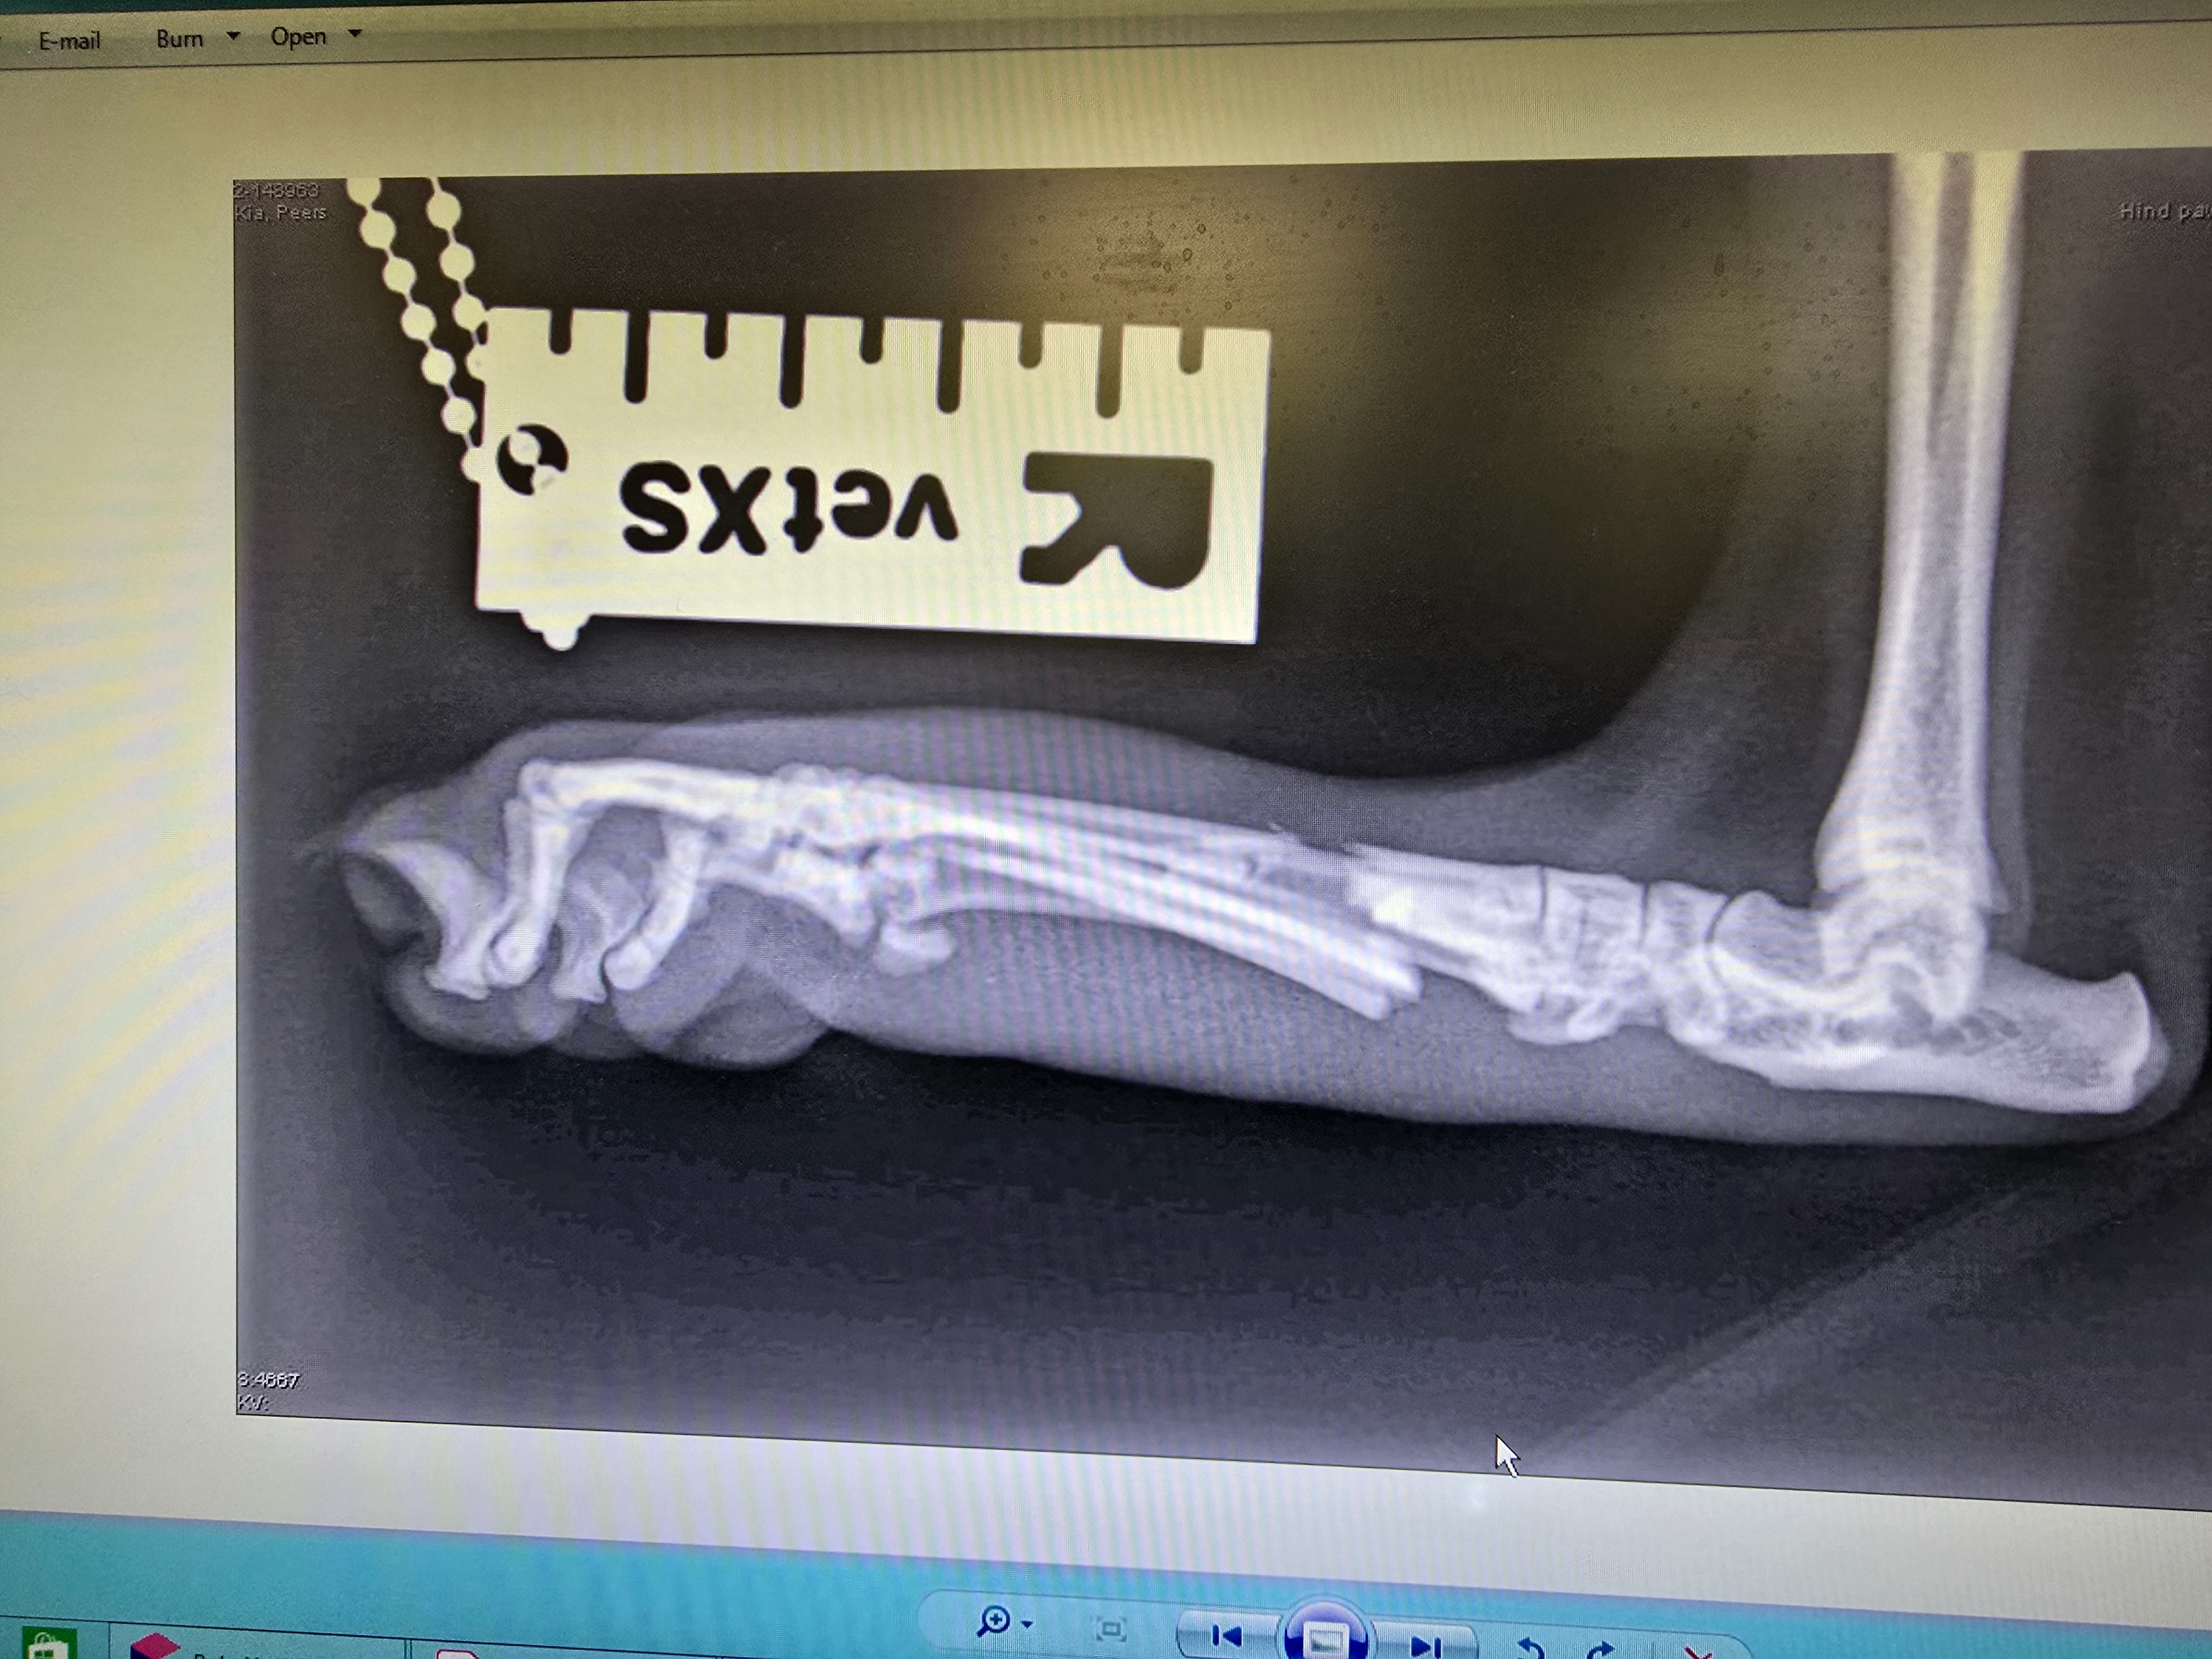

Kai had his surgery to pin his toes and it has failed. We have used all his pet insurance allowance and now he needs another big surgery to put plates and screws in to stabilise his foot. His foot had not healed at all and the pins had moved. Despite us following what they said to the letter. We need your help to raise funds so Kai can have this 2nd surgery. its going to cost £1800 plus £1000 for 2 lots of xrays. Any donations already raised was for the prior surgery and xrays.

Hi my name is Connor and partner Seb. Our cat Kai is 8 and a half years old, and somehow he has managed to break 4 toes on his hind leg. He is covered on pet insurance up to 3k but it very likely will not be enough as he is going to need surgery to repair the breaks by having his bones pinned. That is going to cost a minimum of 3k, possibly more, we are still waiting on hearing from the vets, but then there is more vet visits, more xrays and check ups. If you can please donate to help us help Kai. We would all be very grateful. He is a really loveable cat but also cranky. He will struggle to not be able to go outside but for his own good he will need to be crated for a while to recover. We want to help him recover without worrying about how much it might cost.